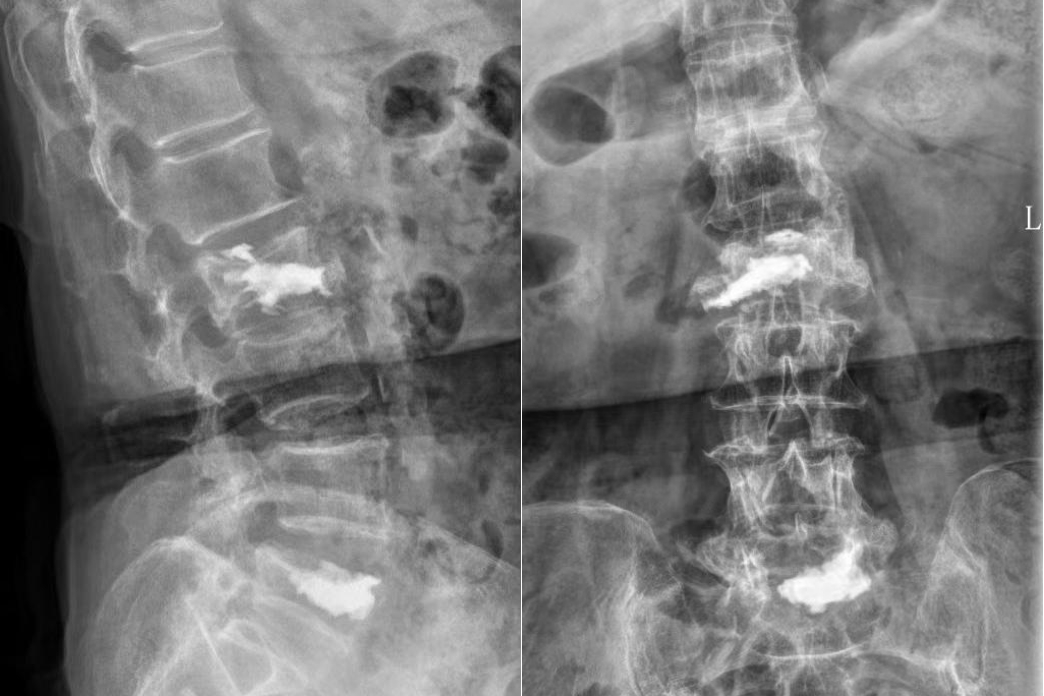

经过3个小时的手术,患者手术顺利,椎体内骨水泥弥散良好,椎管内神经减压彻底。术后患者恢复良好,当天即感觉疼痛缓解。经过2天的术后治疗,患者已经可以正常行走。术后3天,患者平安出院,后续接受康复治疗。

▲术后X线,椎体内骨水泥弥散良好